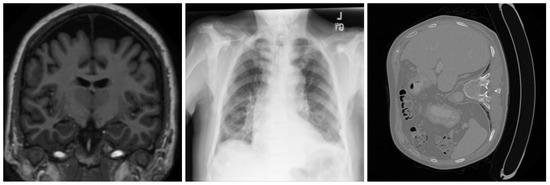

Ensuring the integrity of medical images is essential to securing clinical workflows, telemedicine platforms, and healthcare IoT environments. Existing watermarking and reversible data-hiding approaches often modify pixel intensities, reducing diagnostic fidelity, introducing embedding constraints, or causing instability under compression and format conversion. This [...] Read more.

Ensuring the integrity of medical images is essential to securing clinical workflows, telemedicine platforms, and healthcare IoT environments. Existing watermarking and reversible data-hiding approaches often modify pixel intensities, reducing diagnostic fidelity, introducing embedding constraints, or causing instability under compression and format conversion. This work proposes a distortion-free, non-embedding authentication framework that leverages the inherent stability of the most significant bit (MSB) patterns in the Non-Region of Interest (NROI) to construct a secure and tamper-sensitive reference for the diagnostic Region of Interest (ROI). The ROI is partitioned into fixed blocks, each producing a 256-bit SHA-256 signature. Instead of embedding this signature, each hash bit is mapped to an NROI pixel whose MSB matches the corresponding bit value, and only the encrypted coordinates of these pixels are stored externally in a secure database. During verification, hashes are recomputed and compared bit-by-bit with the MSB sequence extracted from the referenced NROI coordinates, enabling precise block-level tamper localization without modifying the image. Extensive experiments conducted on MRI (OASIS), X-ray (ChestX-ray14), and CT (CT-ORG) datasets demonstrate the following: (i) perfect zero-distortion fidelity; (ii) stable and deterministic MSB-class mapping with abundant coordinate diversity; (iii) 100% detection of intentional ROI tampering with no false positives across the six clinically relevant manipulation types; and (iv) robustness to common benign Non-ROI operations. The results show that the proposed scheme offers a practical, secure, and computationally lightweight solution for medical image integrity verification in PACS systems, cloud-based archives, and healthcare IoT applications, while avoiding the limitations of embedding-based methods. Full article